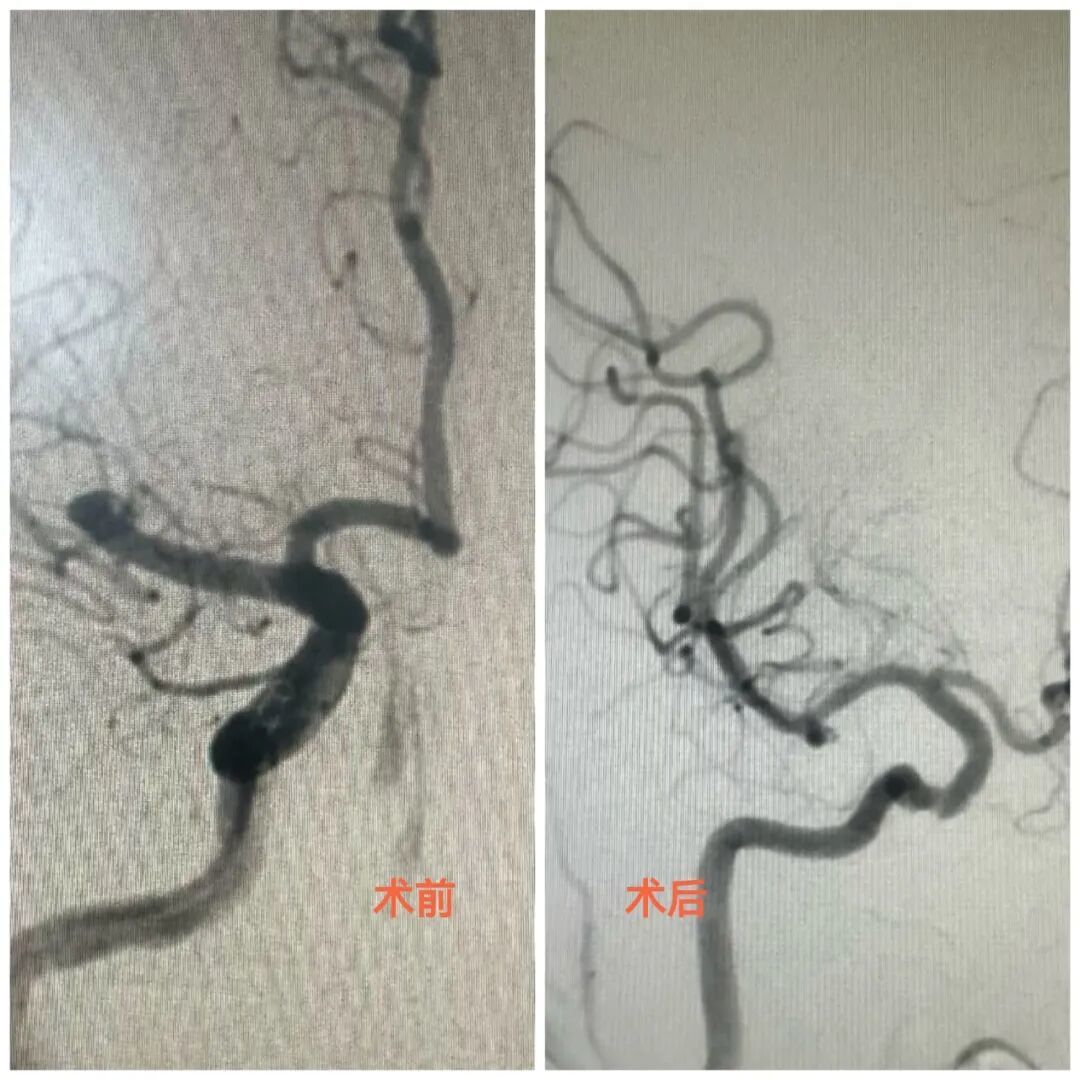

贾颐教授接到会诊电话后连夜赶到医院,与骨科团队进行多学科紧急评估后,果断决定将患者转入神经内科,并在凌晨3点为其施行动脉取栓手术。手术同样取得成功,堵塞血管被开通,郭女士转危为安,目前生命体征平稳。